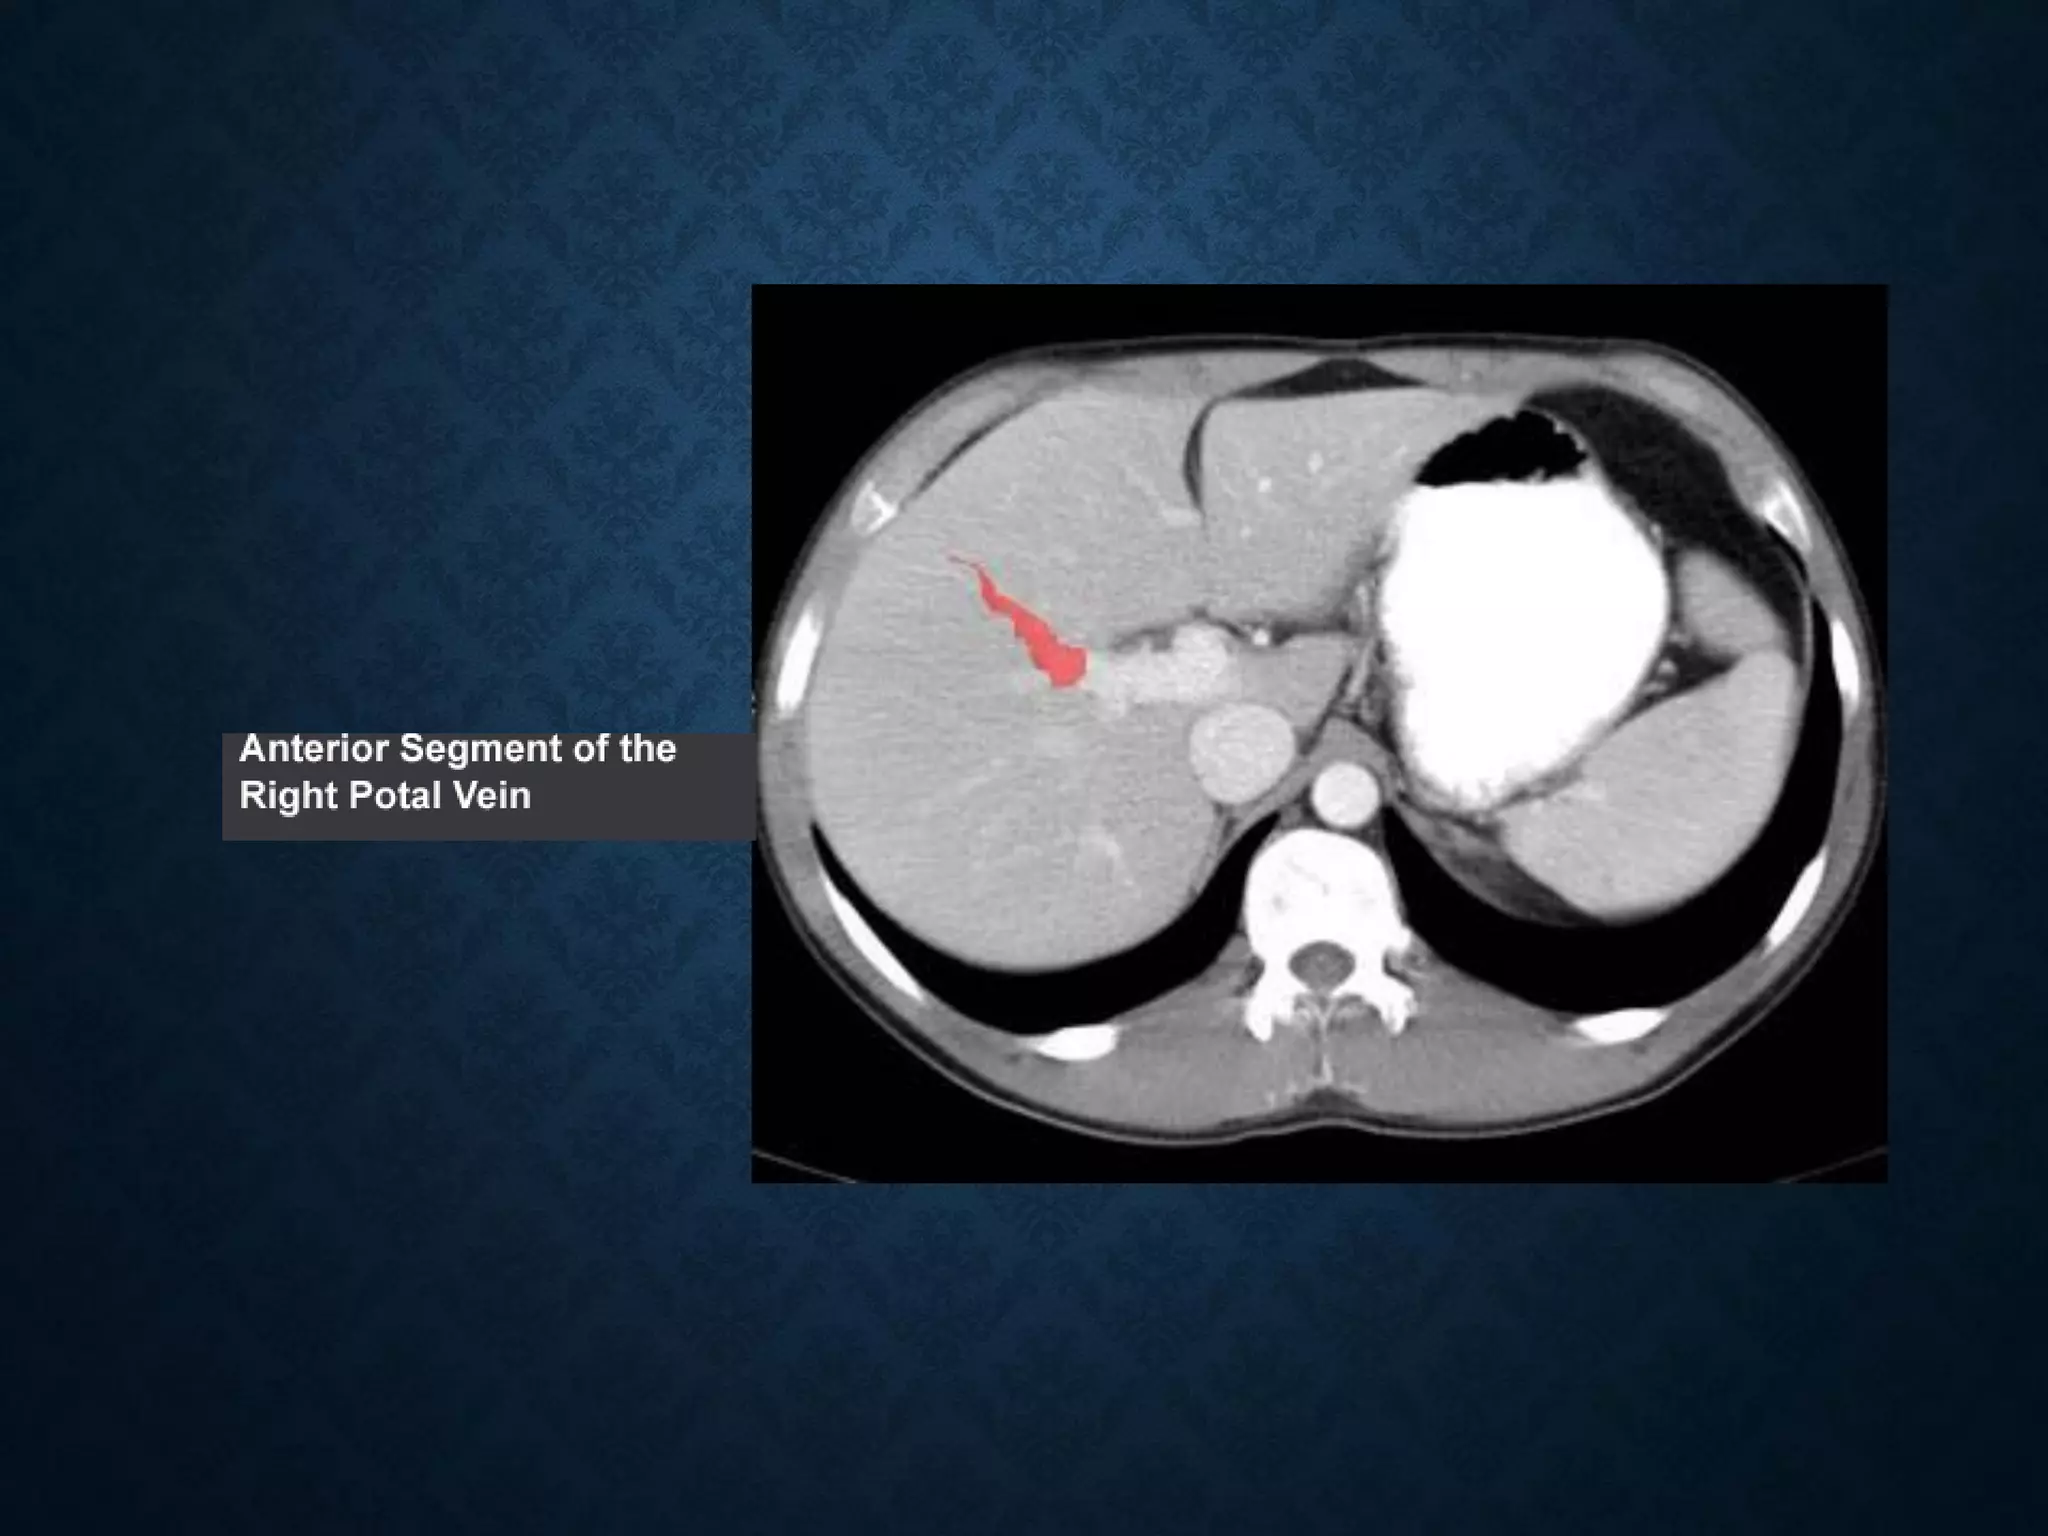

Identify the following structures in the body CT to the right. To view the location of the structure in the image click on

the label at the left and the structure will be indicated in the image. Abdominal CT scans typically begin just above

the diaphragm, so the first slice you see is of the lower chest.